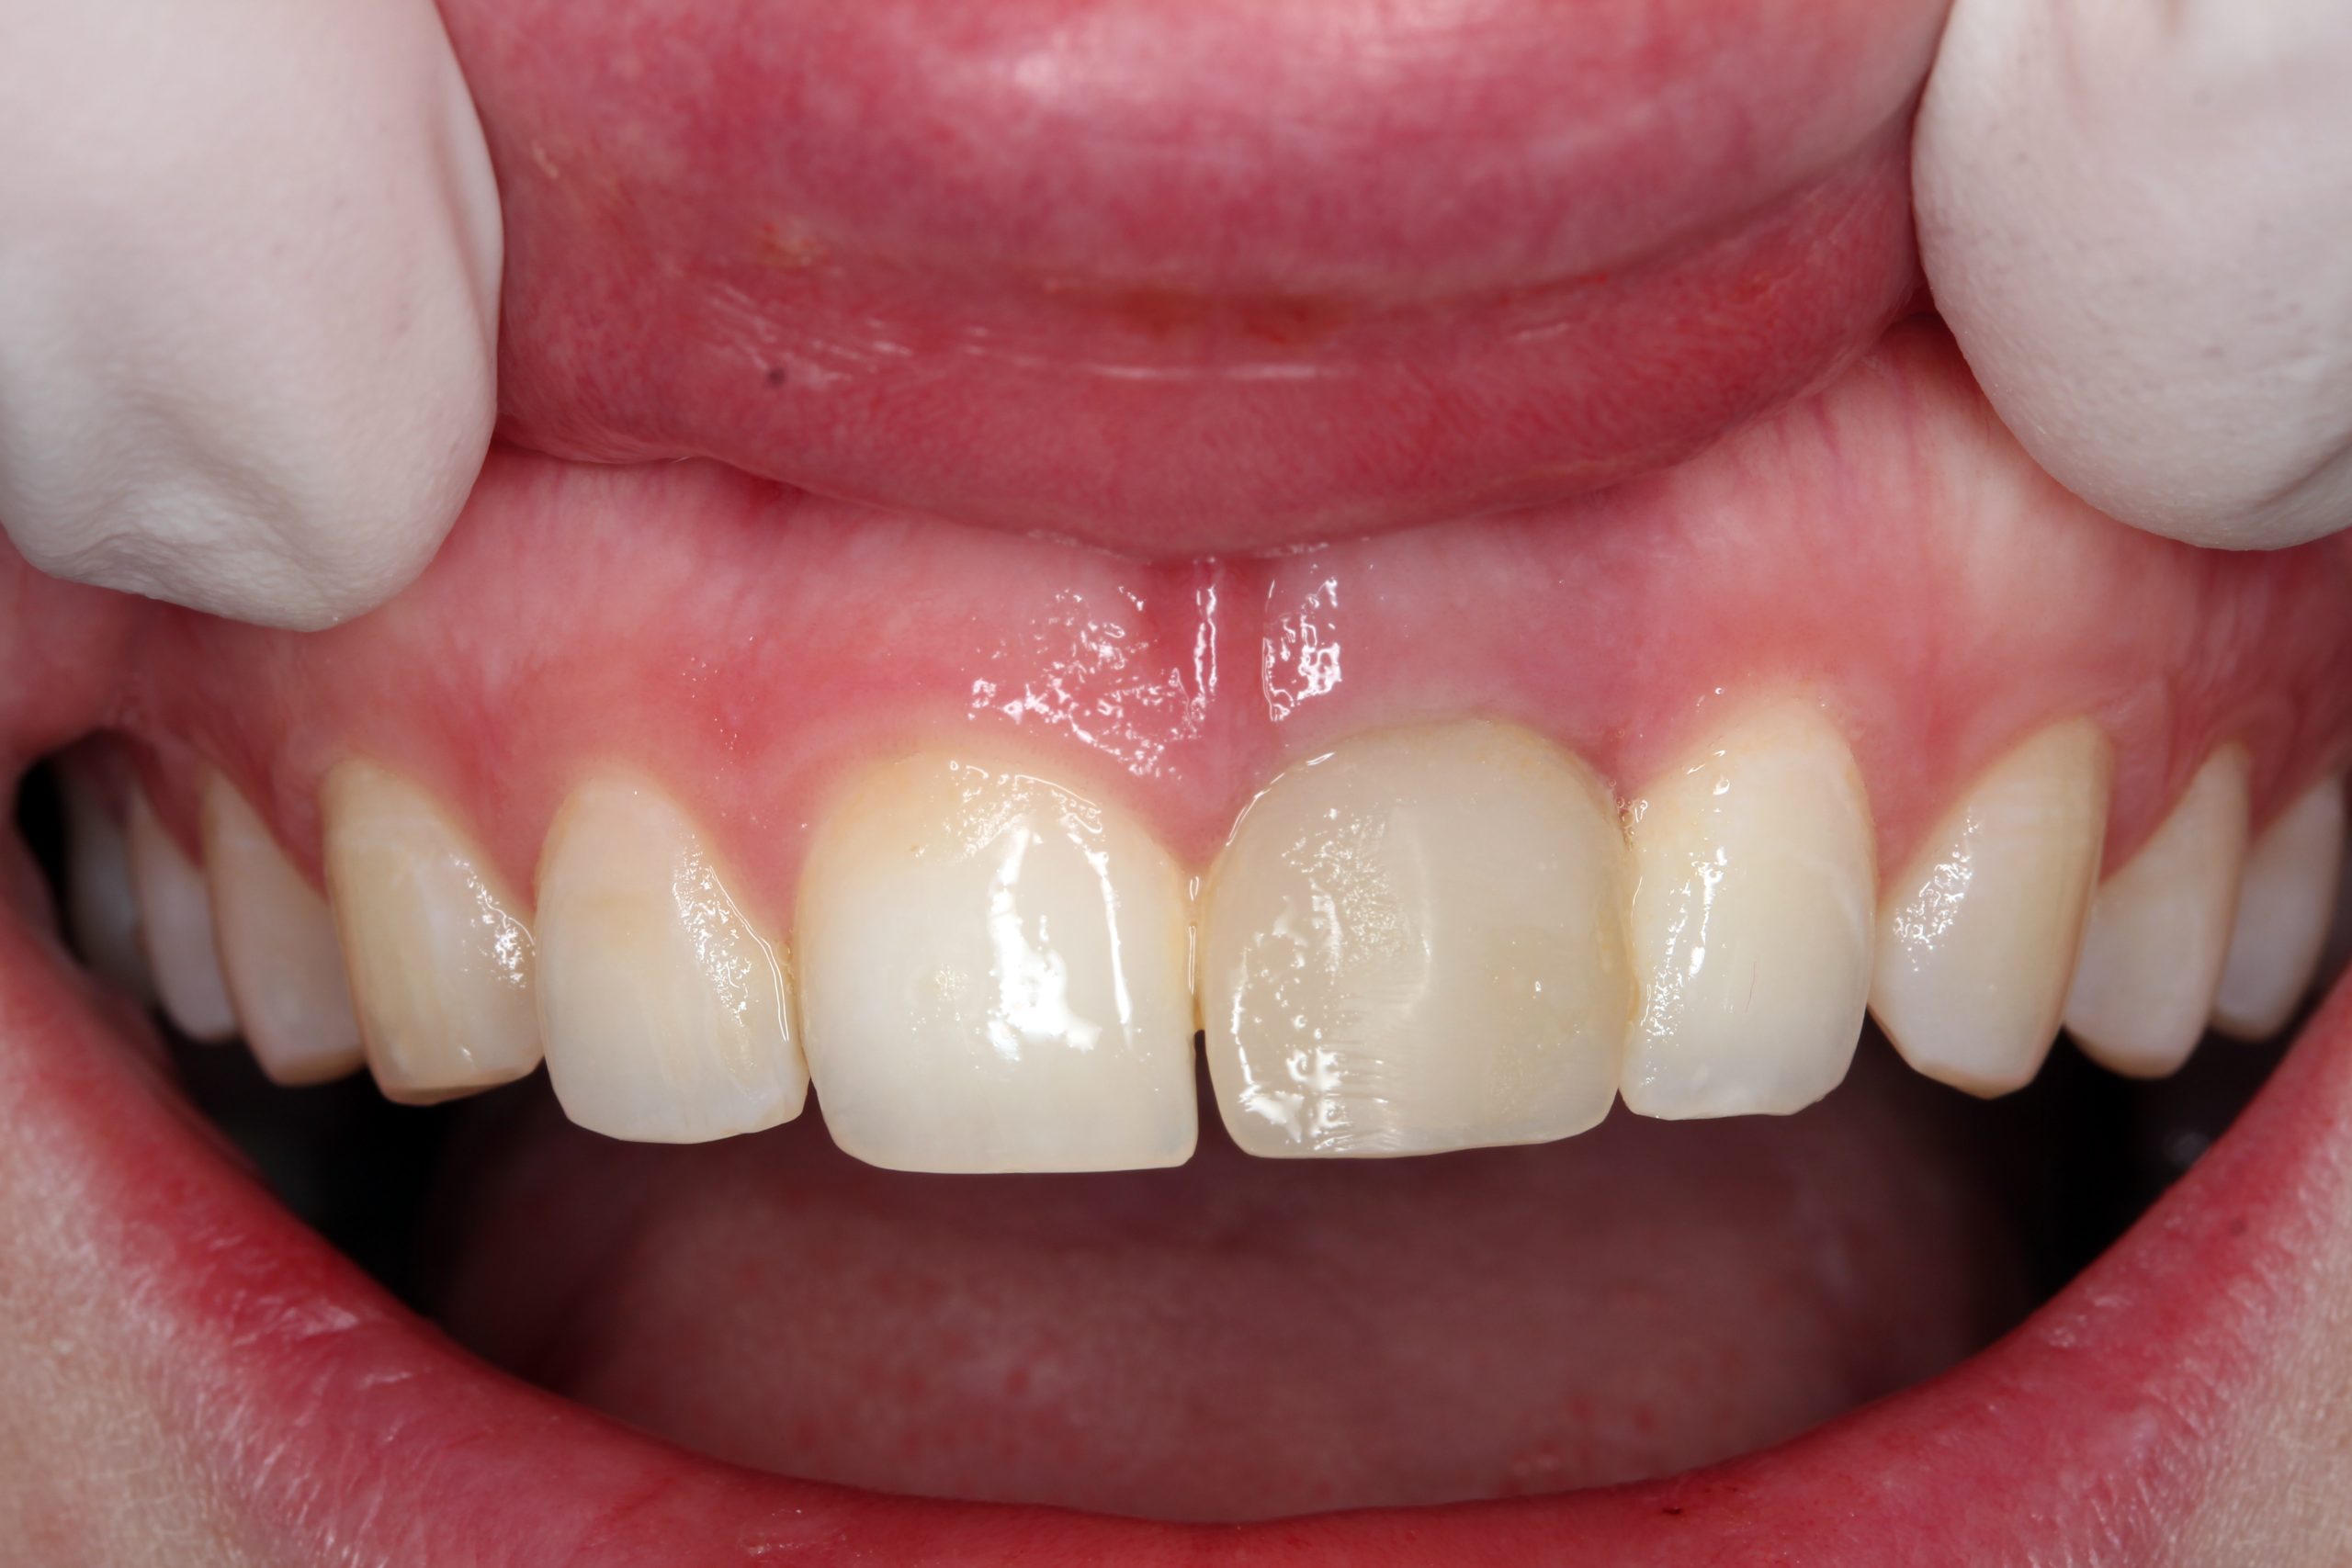

Bei dem Follow-up nach einem Monat sind keine Probleme aufgetreten. Der provisorische Zahnersatz war in das umgebende Gewebe integriert und die Ästhetik des Weichgewebes ist erhalten worden.

Vier Monate nach der Implantation und der Sofortbelastung wurde die provisorische Krone entfernt. Eine vollkeramische Krone wurde im Labor angefertigt.